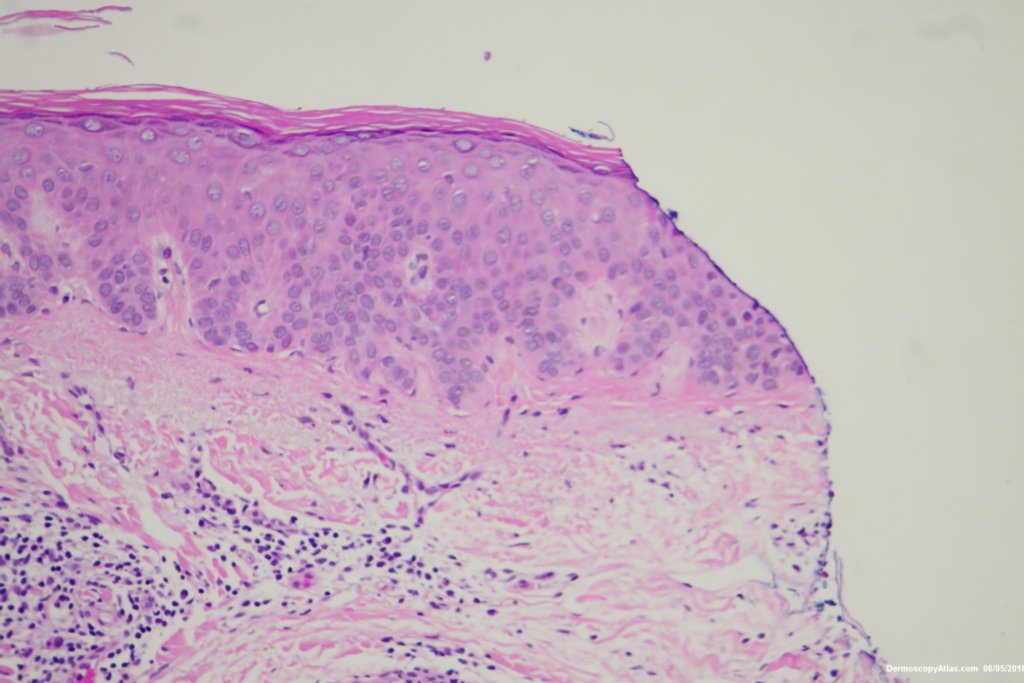

Diagnosis: Pigmented Intraepidermal carcinoma

Some pigmented lesions look melanocytic, However this is a pigmented intraepidermal carcinoma. Some areas show more full thickness atypia than others. The dermatoscopy shows some dots in rows but there are other grey dots showing regression at one edge.